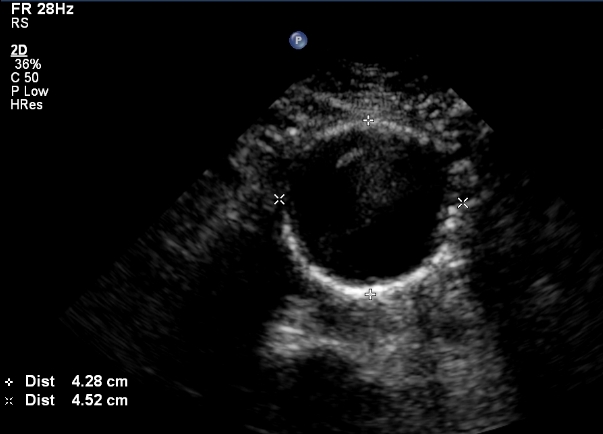

The most available and harmless imaging measure for diagnosis of an abdominal aortic aneurysm is duplex ultrasound. It is recommended that every man age 65-75 who has ever smoked be screened at least once for an AAA with an ultrasound examination. Some advocate screening for any man over age 65 and any woman over age 65 who has ever smoked, as well. The USPSTF recommends screening men aged 65-75 who have ever smoked for abdominal aortic aneurysm with ultrasound and claim data is inconclusive regarding AAA screening in women. Interestingly all these guidelines do not address AAA screening in first degree relatives of patients that have aneurysms, despite known familial clustering of some types of aneurysms. Screening has been shown to prevent death and be cost effective, after a follow-up of 7 and 10 years.

We only offer procedures when an aneurysm is large, or when it is associated with symptoms. Otherwise, we follow them. The most common way to follow an aortic aneurysm is with an ultrasound. This is either done once a year, or every 6 months for larger aneurysms. Sometimes, we use CT or MRI.